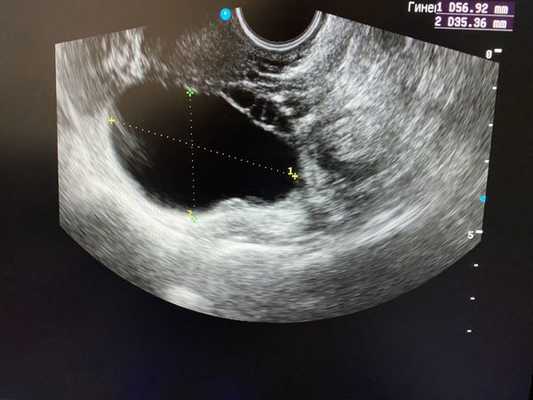

- Киста жёлтого тела образуется из не подвергшегося инволюции жёлтого тела, в котором может происходить скопление серозной или геморрагической жидкости. КЖТ имеет утолщённые стенки.

Ультразвуковое исследование органов малого таза является наиболее простым и высокоинформативным методом диагностики различных кист яичников.

Как выглядят яичники при наличии кист:

Безусловно, проведение ультразвуковой диагностики трансабдоминальным и трансвагинальным датчиками позволит не только выявить локализацию кисты, но и определить ее структуру, размеры, характер жидкостного содержимого, определить тактику лечения пациентки. Особенностью фолликулярных кист при ультразвуковом исследовании является тонкостенная капсула с отсутствием сосочков внутренней стороны капсулы. [10] Диагностировать кистозные образования у беременных женщин значительно труднее, ввиду увеличения размеров матки на соответствующих сроках беременности, поэтому ультразвуковое исследование стоит проводить с ЦДК и доплерометрией [11] .